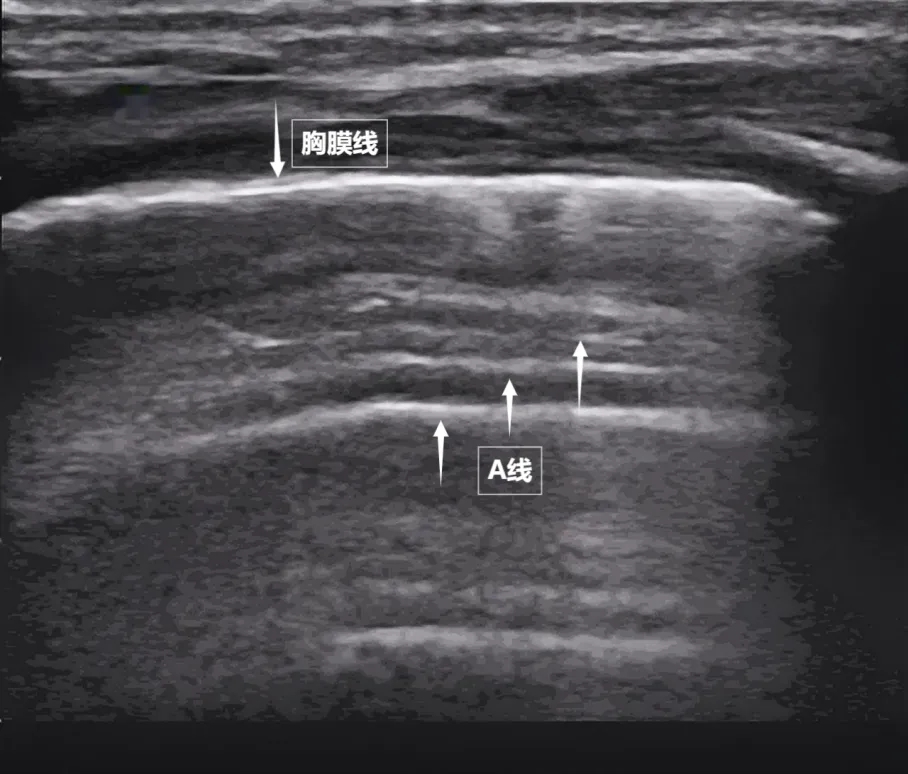

第一景:“海岸线与海浪”——胸膜线与A线

当声波穿过胸壁肋骨缝隙,首先会遇到紧贴肺表面的光滑薄膜——壁层胸膜和脏层胸膜。两者紧密相贴,中间没有多余的气体或液体。它们在屏幕上呈现为一条明亮、光滑的水平线,共同构成了胸膜线。这条线就是肺的“海岸线”。在它的下方,由于肺泡内大量气体对声波的强烈反射,会出现一系列与胸膜线平行的、等间距的、重复出现的明亮平行线,像海浪般不断向屏幕深处延伸,这就是A线(见下图)。A线是正常含气肺部的典型标志。它的存在直接提示肺表面含气充足,胸膜腔内无异常积液或气体。

图为正常新生儿肺部超声表现。